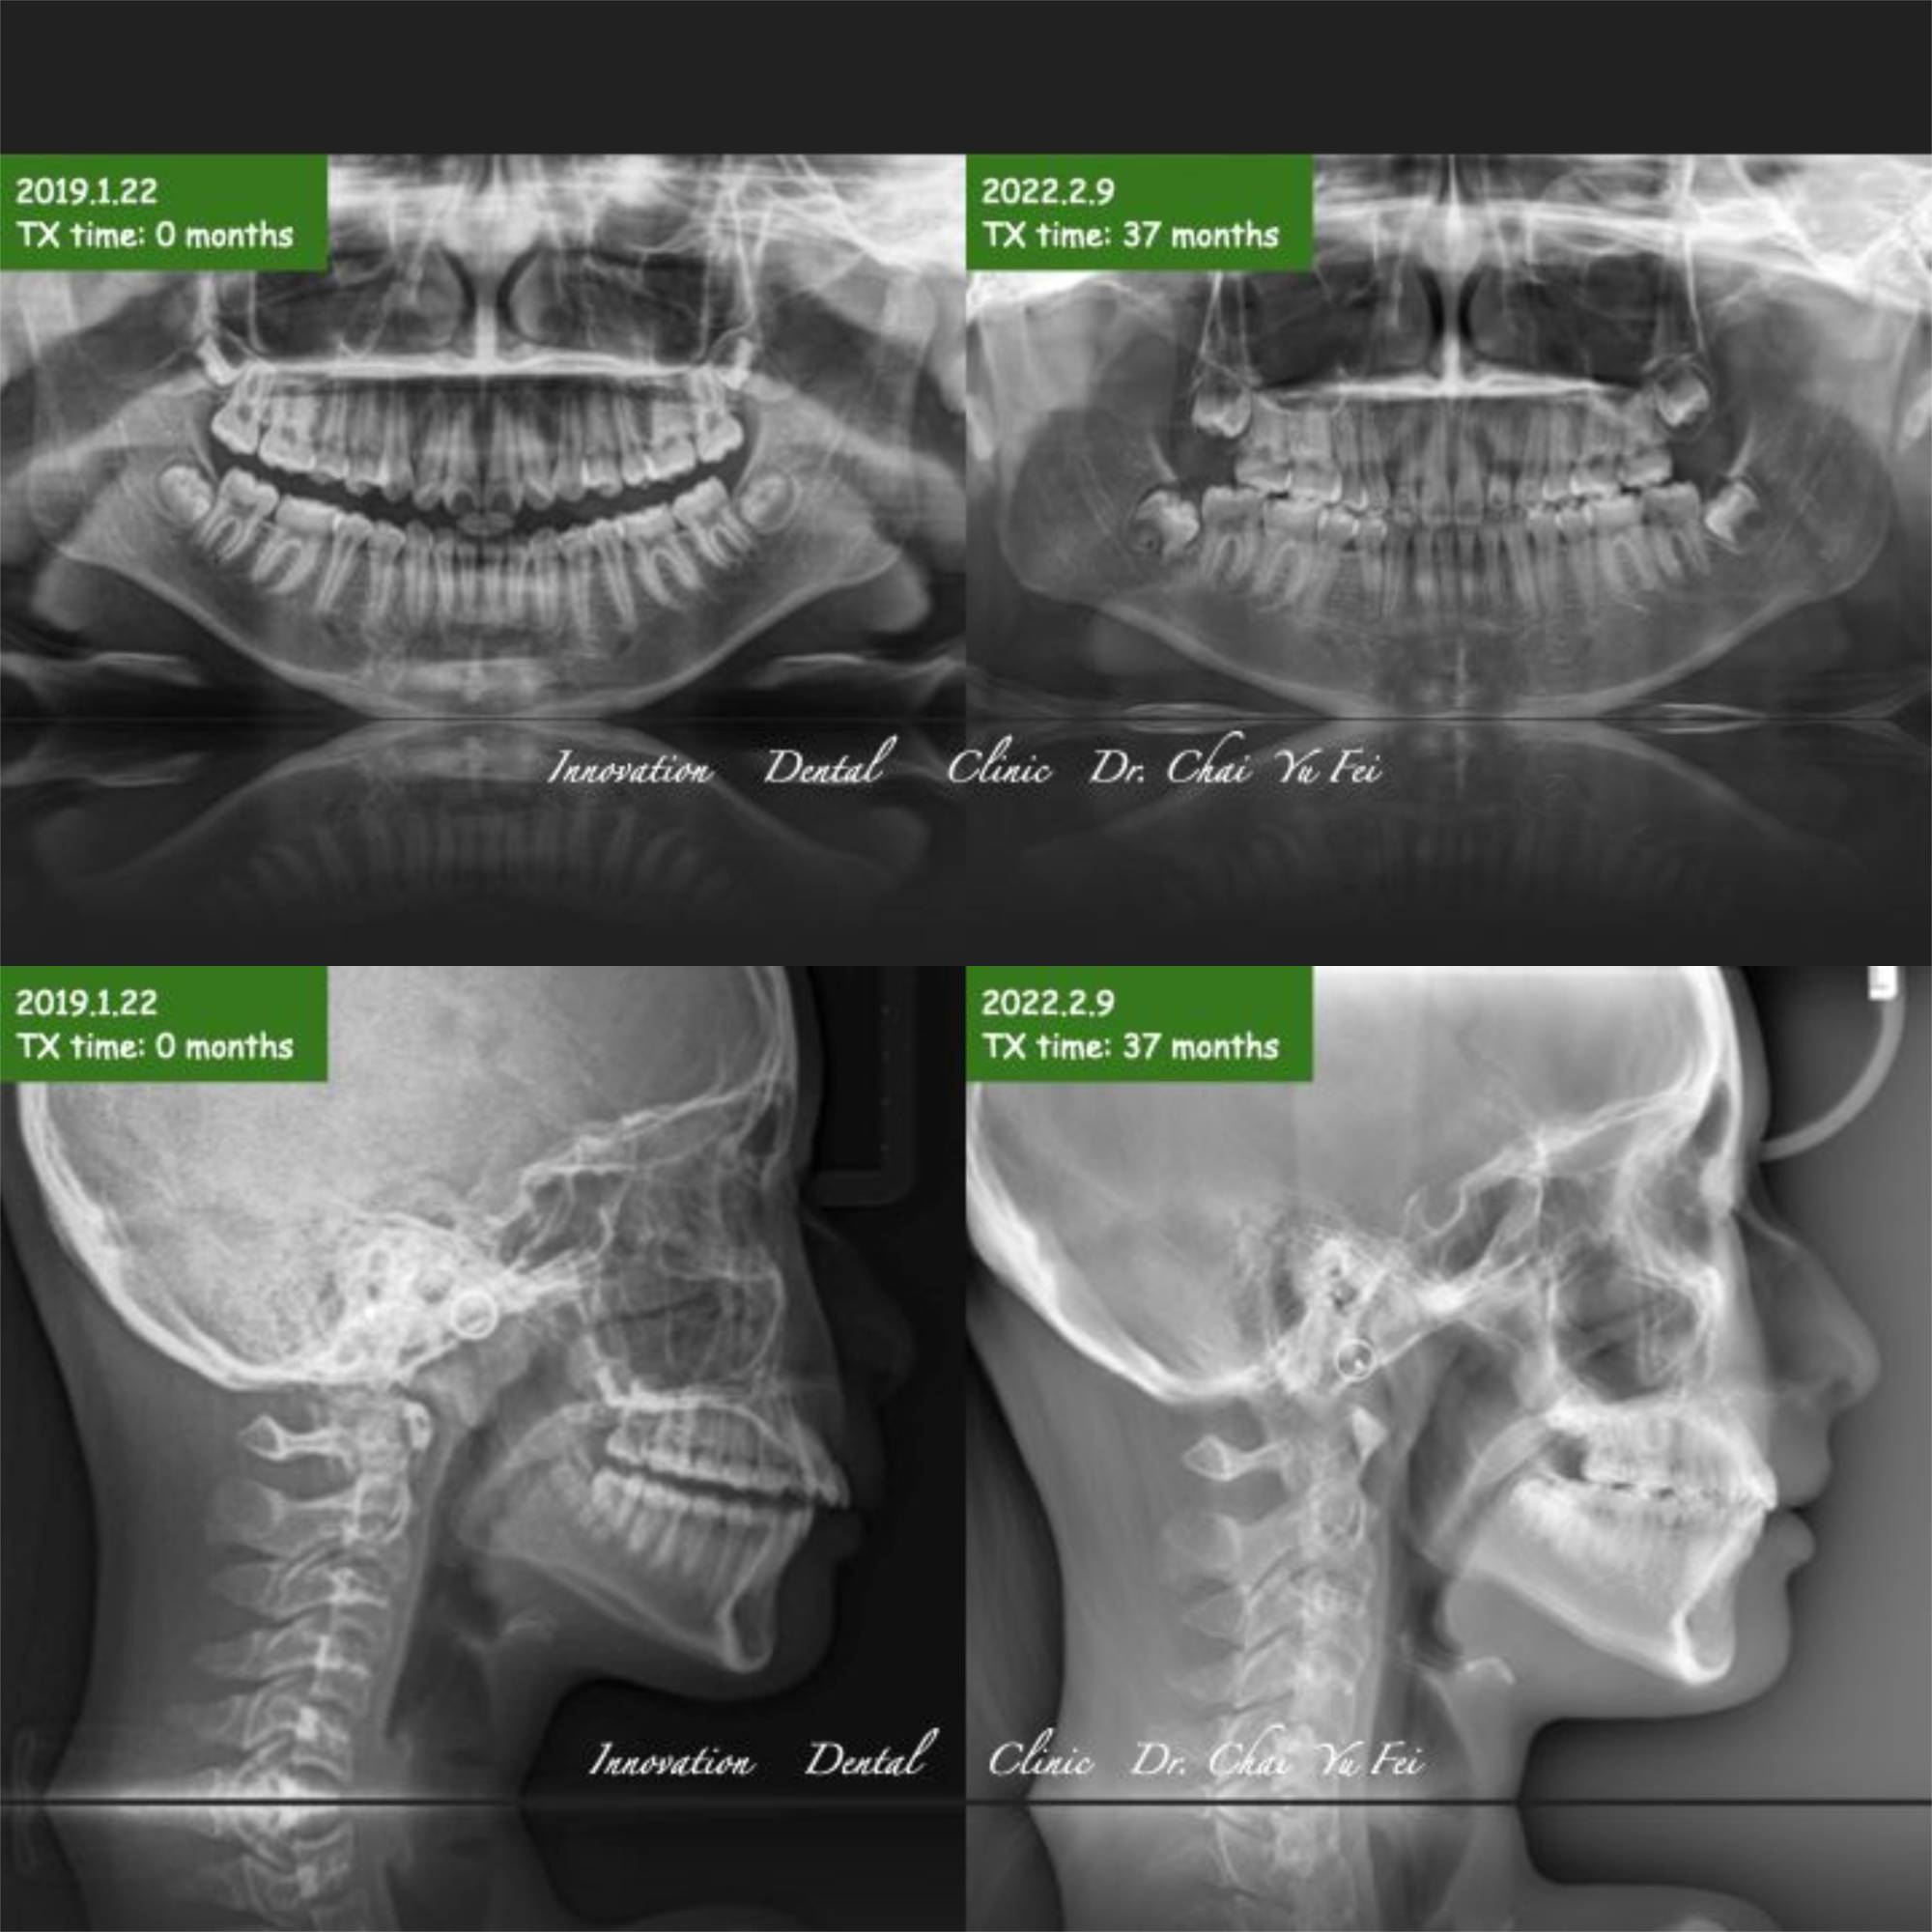

以這次分享的邱同學案例來說,經過翟醫師評估,判定她的上下顎骨骼都是正常的位置,是門牙外翻造成的齒性暴牙。

果然,在翟醫師的治療之下,患者原本前凸跟狹窄的上顎齒列,藉由上顎2顆小臼齒移除之後,暴牙的感覺完全消失,下顎也伴隨她的生長發育跟橡皮筋進行的下顎牽引,我們得到了一個很好的輪廓~最後的成果讓人很感動。

最後分享邱同學的矯正成果給大家參考: